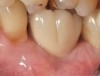

Problem: The implant is placed too facial with significant recession on the midfacial aspect of the abutment and/or crown; the implant is healthy and the patient has a high smile line with an intermediate to thick periodontal phenotype (Figure 1 and Figure 2).17-19

Fig 1. Midfacial recession can affect the esthetics of a smile and lead to an unsatisfactory outcome.

Fig 2. The cause for midfacial recession is excessive labial implant placement. Secondary to poor placement is overcontouring of the implant abutment.